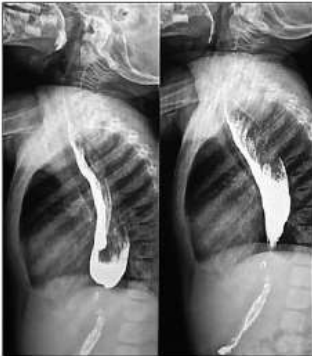

Menina de 8 anos apresenta, há 2 anos, disfagia, regurgitação e perda de peso. Há 6 meses apresenta dor retroesternal e pirose. Após anamnese, exame físico e exames laboratoriais, foi realizado o esôfago-estomago-duodeno (EED) contrastado, com as seguintes imagens:

Analise as afirmativas abaixo sobre a principal hipótese diagnóstica.

I. Esofagite Eosinofílica.

II. Acalasia do cárdia.

III. Doença do refluxo gastroesofágico.

IV. Estenose pilórica.

Estão corretas as afirmativas: